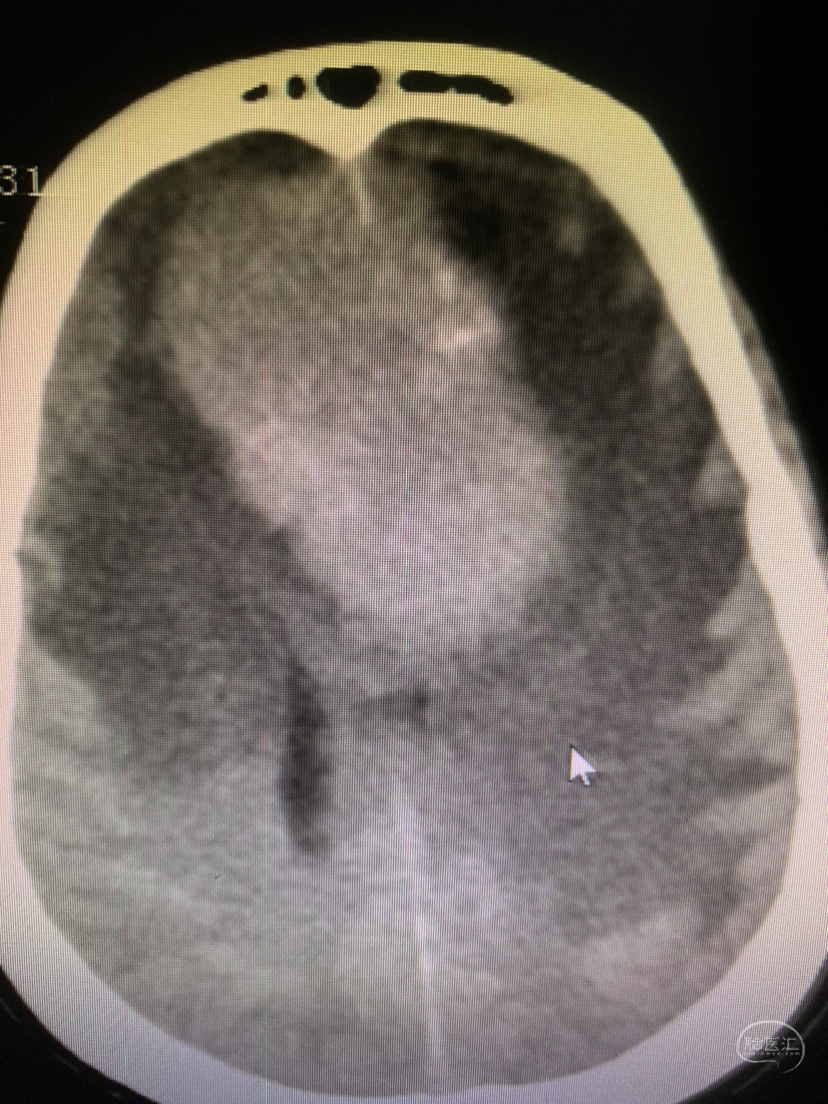

术前CT

术前CT